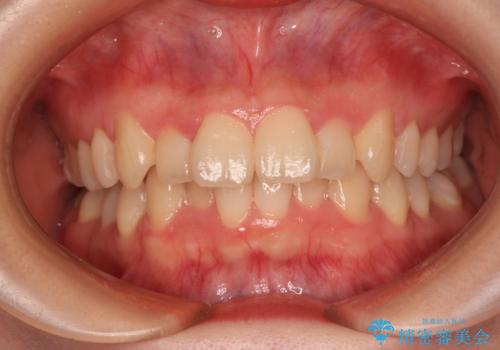

長年気になっていた前歯 矯正治療と補綴治療による審美歯科治療